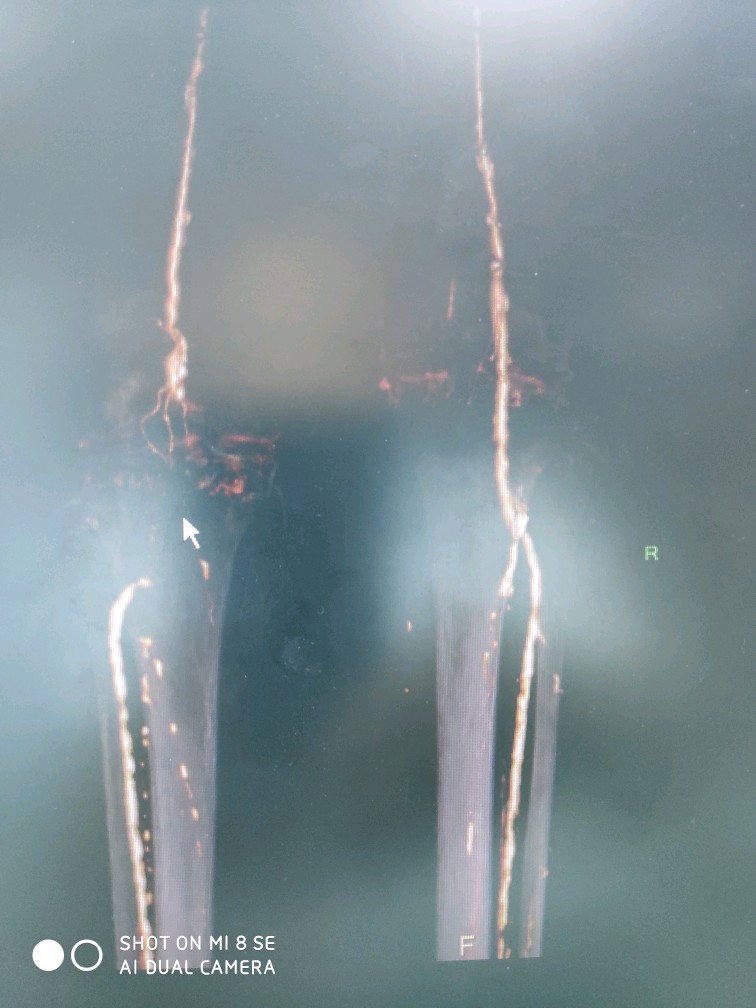

下肢动脉硬化闭塞症

下肢动脉硬化闭塞症,常发生于老年患者,与高血压,糖尿病,高血脂,吸烟等关系密切。早期临床表现肢体皮温发凉,随后导致间歇性跛行(走路疼痛伴随离距缩短,休息缓解),晚期表现为足趾颜色发黑,溃烂。

中晚期患者单纯保守治疗无效,尝尝需要外科手术干预。目前,本团队已成功开展球囊扩张,支架植入,斑块旋切等多种微创治疗术式,跻身国内一流水准!